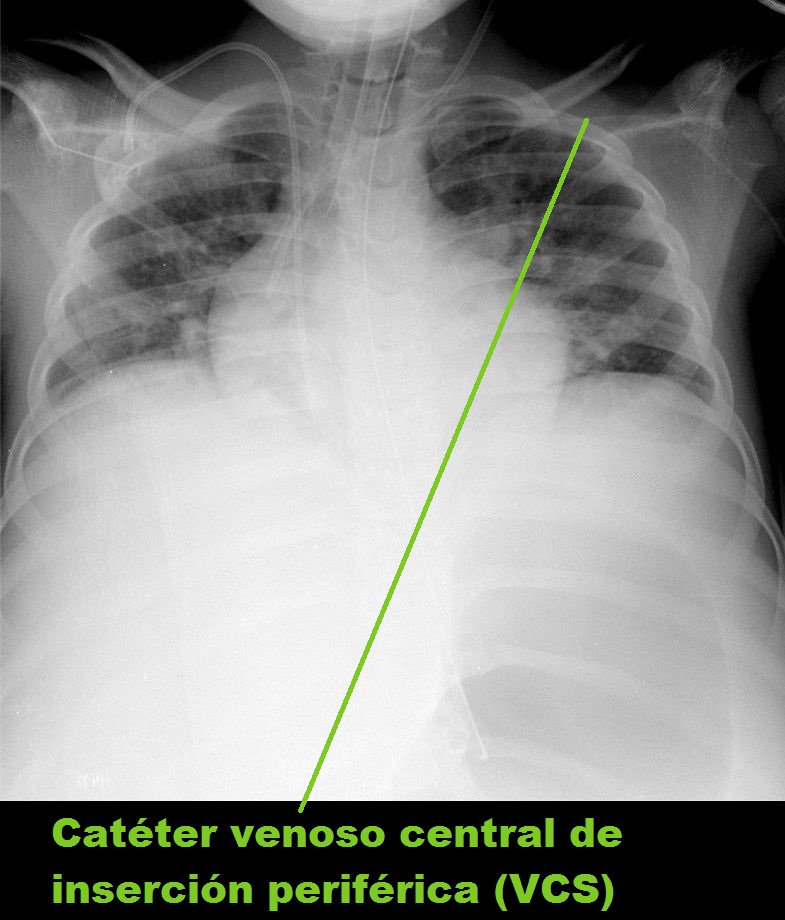

Los catéteres venosos centrales, ya sean de inserción central o periférica, deben quedar con sus extremos también próximos a la unión de la vena cava superior (VCS) con la AD.

• Catéter venoso central de inserción periférica (VCS)